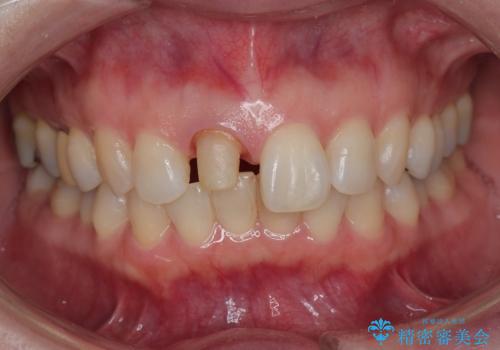

- 前歯が気になるとの事で来院。保険の被せ物(プラスチック素材)メタルの土台が入っていたので

拡大鏡下で全て除去し精密根管治療を行いセラミックの被せ物を装着しました。